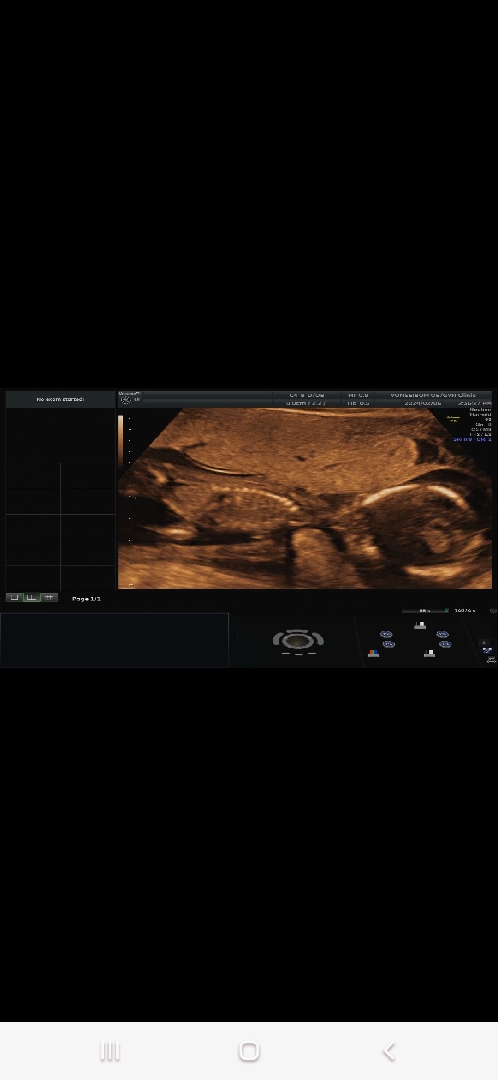

아기가 자궁에 낑겨있는거 같아요ㅠㅠ

16주 초음파인데 14주부터 낑겨있더니 여전히 낑겨있네용..ㅎㅎ 저러다 머리 껴서 잘못되는건 아닌가 싶어서 괜한 걱정만 하고 있네요 우리 띠용이 저러고 있어도 괜찮겠죠?!

어머 제 초음파인줄 알았어요! 태반이 엄청 두꺼워서 저도 저렇게 낑겨있는데… 마지막으로 초음파보고 3주가 지났는데 걱정돼요ㅠㅠ 농담이 아니라 진짜로 아기가 터지면 어쩌나 싶고ㅠㅠ 아기가 터지기 전에 양수가 먼저 터지겠죠?ㅠㅠ

엇 저도 저랬었는데 선생님께 여쭤보니 양수도 충분하고 확대해서(?) 보셔서 그렇다고 괜찮다고 하시더라구요! 걱정되심 그래도 한번 여쭤보세요!!!

저도 초기에 자궁 작다고하시고.. 자궁이 뒤에 있는 후굴이라고 하시고 또 17주에 저렇게 낑겨있게 보여서 걱정했는데 아이를 근접촬영하지않고 멀리서 찍으니까 아기 발 밑에 공간이 꾀 있더라구요ㅎㅎㅎ 그런데 원래 점점 커가면서 아기가 웅크리는 자세가 되니까요~ 걱정 안하기로 했어요!